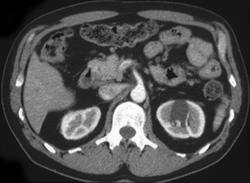

Acute tubular necrosis (ATN) Secondary to Angiogram